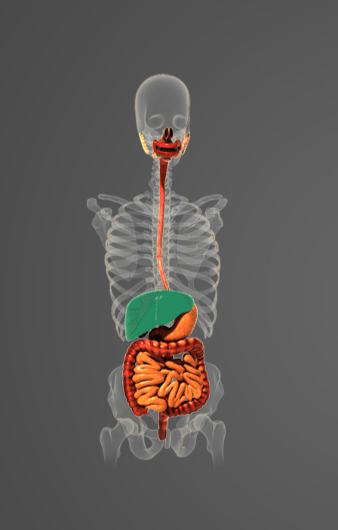

-

Question ofReklama

Určete:

-

lalok spánkový

-

mozeček

-

mozkový kmen

-